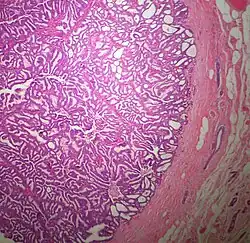

Microscopic histopathological analyses of SPC lesions (refer to adjacent high-power photomicrograph) generally show tumors with multiple circumscribed nodules of expanded ducts filled with neoplastic epithelial cells which may appear spindle-shaped or plasma cell-like, have red to pink cytoplasm due to the uptake of eosin after staining with hematoxilin & eosin, and eccentrically-placed nuclei. Rarely, signet ring-shaped cells are present. The tumors may have cystic and hemorrhagic areas. Myoepithelial cells are found within and at the periphery of these tumors. The papillary architecture seen in the other SCB types is in general not apparent; rather, pseudo-rosettes (i.e. radial arrangements of neoplastic cells around small blood vessel) and nuclear palisading (i.e. parallel arrangements of the nuclei in rows of tumors that resembles picket fences) around stromal cores (i.e. supporting tissues) may be seen. SPC tumor tissues typically (>50% of cases) have areas of neuroendocrine differentiation. The presence of these areas strongly supports the diagnosis of SPC.[21] The signet ring-shaped cells in these tumors contain cytoplasmic mucin-containing vacuoles which push their cells' nuclei to one side.[10] Mucin may also occur outside of cells in these lesions. The presence of signet ring-shaped cells bearing mucin-containing vacuoles with or without extracellular mucin strongly supports the diagnosis of SPC. SPC is considered invasive when the tumor nests have a characteristic jigsaw growth pattern with ragged and irregular margins with the loss of myoepithelial cells at the site(s) of invasion.[21] Rarely, invasive SPC occurs with nearby invasive carcinoma of NST, lobular carcinoma, cribriform carcinoma, or tubular carcinoma breast tumors.[3]